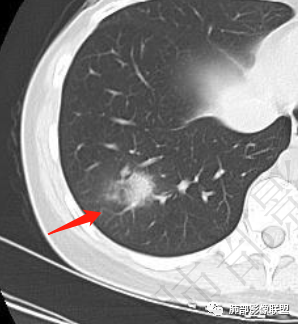

年轻女性,发热,白细胞略低,超敏CRP高,右肺下叶团片影,边缘毛糙,周围见磨玻璃晕,其内含气细支气管,考虑炎性肉芽肿,侵袭性曲霉菌感染?鉴别淋巴瘤

年轻,急性起病,发热伴肺部阴影,考虑感染性病变没问题,无诱因,还是真无诱因,咳嗽无痰,有一些胃肠道症状及乏力。肺部一斑片影,考虑非典型病原菌,治疗无效考虑下特殊病原。这个病程3天,渗出不明显,周围磨玻璃感觉蛮清晰,支气管充气征?鉴别淋巴瘤?

右肺下叶局限性实变影伴晕征。

影像轻,临床重,结合炎性指标,需考虑非典型肺炎(鹦鹉热衣原体可能)

2.影像特征:右肺下叶局限性实变影伴晕征,边界不清,内部支气管尚通畅,实变区密实区边缘稍膨隆。符合炎性病灶特征。

3.综合分析:急性病程,炎性指标高,常见的是普通社区肺炎,如肺炎链球菌感染等。但本例患者临床表现较重,应先表现相对较轻,白细胞不高,须考虑非典型肺炎的可能性。本例隐球菌荚膜实验阴性,而军团菌临床症状一般较重,影像分布也更广泛、进展迅速,多器官损害更明显。因此考虑鹦鹉热衣原体可能性更大一些。其他如腺病毒等感染也是需要排除的。